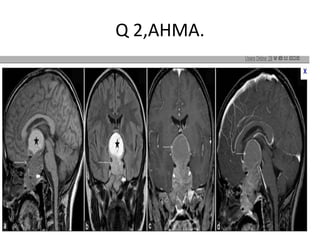

Q 2,AHMA.

2 G.